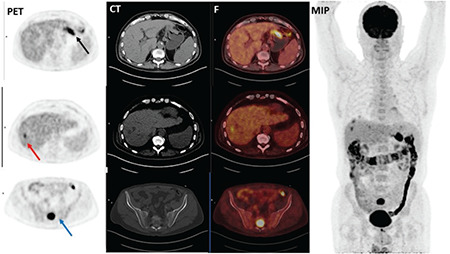

Primary tumor FDG uptake was observed in all the subjects except 2 patients with SRCC. Therefore, the analysis was performed according to semiquantitative analysis instead of visual evaluation. Mean ± standard deviation SUVmax obtained from 339 patients with 18F-FDG accumulation in primary tumor was 12.9±8.6 in PET/CT imaging. The highest SUVmax was detected in patients with medullary subtype GC (17.8±9.9) while the lowest SUVmax (9.7±7.6) was seen in SRCC. A statistically significant difference was documented among all histological types based on 18F-FDG uptakes (p<0.001), and the primary tumor SUVmax was found statistically higher in patients with TAC (14.5±8.8) than in patients with SRCC (p<0.001) (Table 1) (Figure 1 and 2).

Figure 1.

A 68-year old male patient with gastric tubular adenocarcinoma. Axial PET (A), CT (B), and fusion (C) images showed high 18F-FDG uptake (SUVmax: 13.29) in primary tumor in the fundus of the stomach (black arrow). Liver metastasis showed increased 18F-FDG uptake (short axis diameter: 1.88 cm, SUVmax: 6.24) (red arrow). Additionally, bone metastasis was demonstrated in PET/CT images (SUVmax:16.29) (blue arrow)

18F-FDG: Fluorine-18-fluorodeoxyglucose, SUVmax: Maximum standardized uptake value, MIP: Maximum intensity projection image, PET: Positron emission tomography, CT: Computed tomography